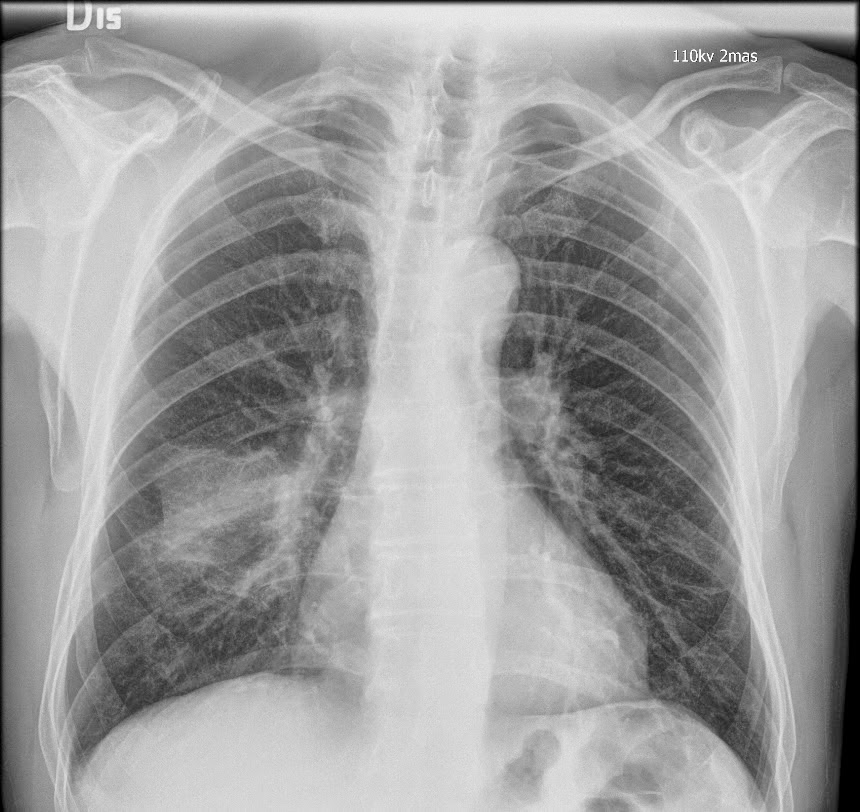

Caso interesante #6

Otro casito de un tórax para localizar la consolidación